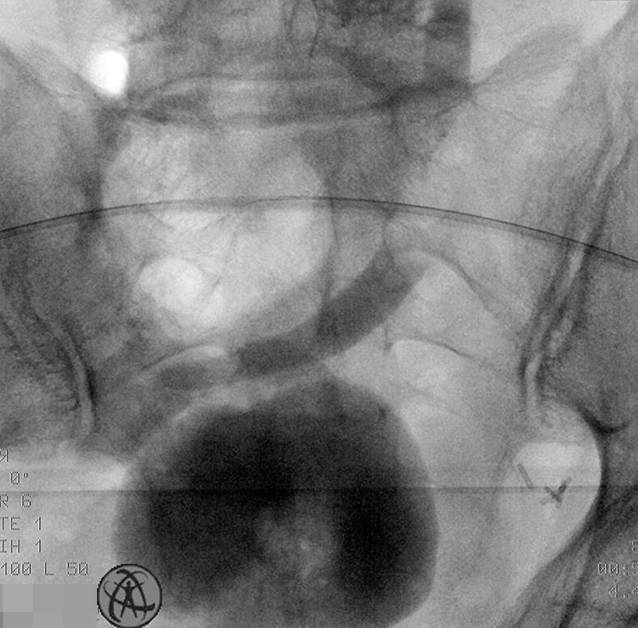

Im weiteren Verlauf wurde der Patient geplant zum Rendez-vous-Verfahren aus Kolonoskopie und antegrader Ureterorenoskopie für ein endoskopisches Realignment aufgenommen, wo es gelang, nach Vorlegen eines Führungsdrahtes einen Gallengangstent in die Ureterenmündung zur kontinuierlichen Dilatation einzubringen (Abb. 3). Unter antibiotischer Abschirmung wurde die perkutane Nephrostomie geklemmt. Der Gallengangstent wurde vom Patienten nach 4 Wochen ausgeschieden, sonographisch zeigte sich weiterhin eine Hydronephrose Grad I links bei unauffälligen Nierenfunktionsparametern.

In nachfolgenden Kontrollen per Röntgen-gestützter, antegrader Ureteropyelographie über die liegende perkutane Nephrostomie konnte ein steter Abfluss über die Ureterenmündung in den Pouch dargestellt werden (Abb. 4). Bei klinischer Beschwerdefreiheit wurde die liegende perkutane Nephrostomie 4 Wochen nach Stentverlust entfernt.